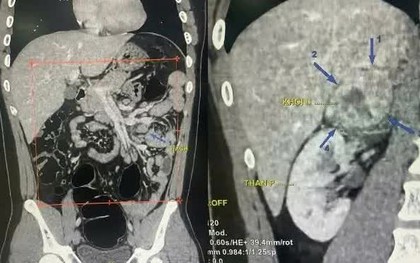

VTV.vn - Nghĩ chỉ do ăn uống thất thường, nam thanh niên 19 tuổi ở Hà Nội đi khám khi tiểu hồng kéo dài và được phát hiện khối u thượng thận kích thước tới 6 cm.